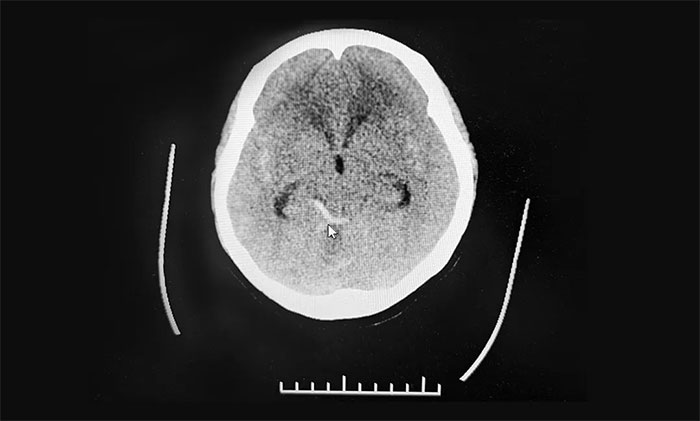

在神经外科6A病区、急诊科、麻醉科等多学科团队努力抢救下,患者意识苏醒,恢复自主呼吸,生命体征均平稳。医护团队抓住时机,遂立即转影像科行头颅CT,显示蛛网膜下腔出血。做完CT检查返回急诊抢救室后,患者再次昏迷,并出现四肢抽搐症状,再次予以抢救。最终,患者意识终于恢复清醒,生命体征平稳,遂转入神经重症监护8A病房。

结合之前的核磁共振检查,上海蓝十字脑科医院神经外科学术副院长、神经外科6A病区主任于耀宇考虑,患者颅内动脉瘤破裂蛛网膜下腔出血并破入脑室。

▲ CT显示蛛网膜下腔出血